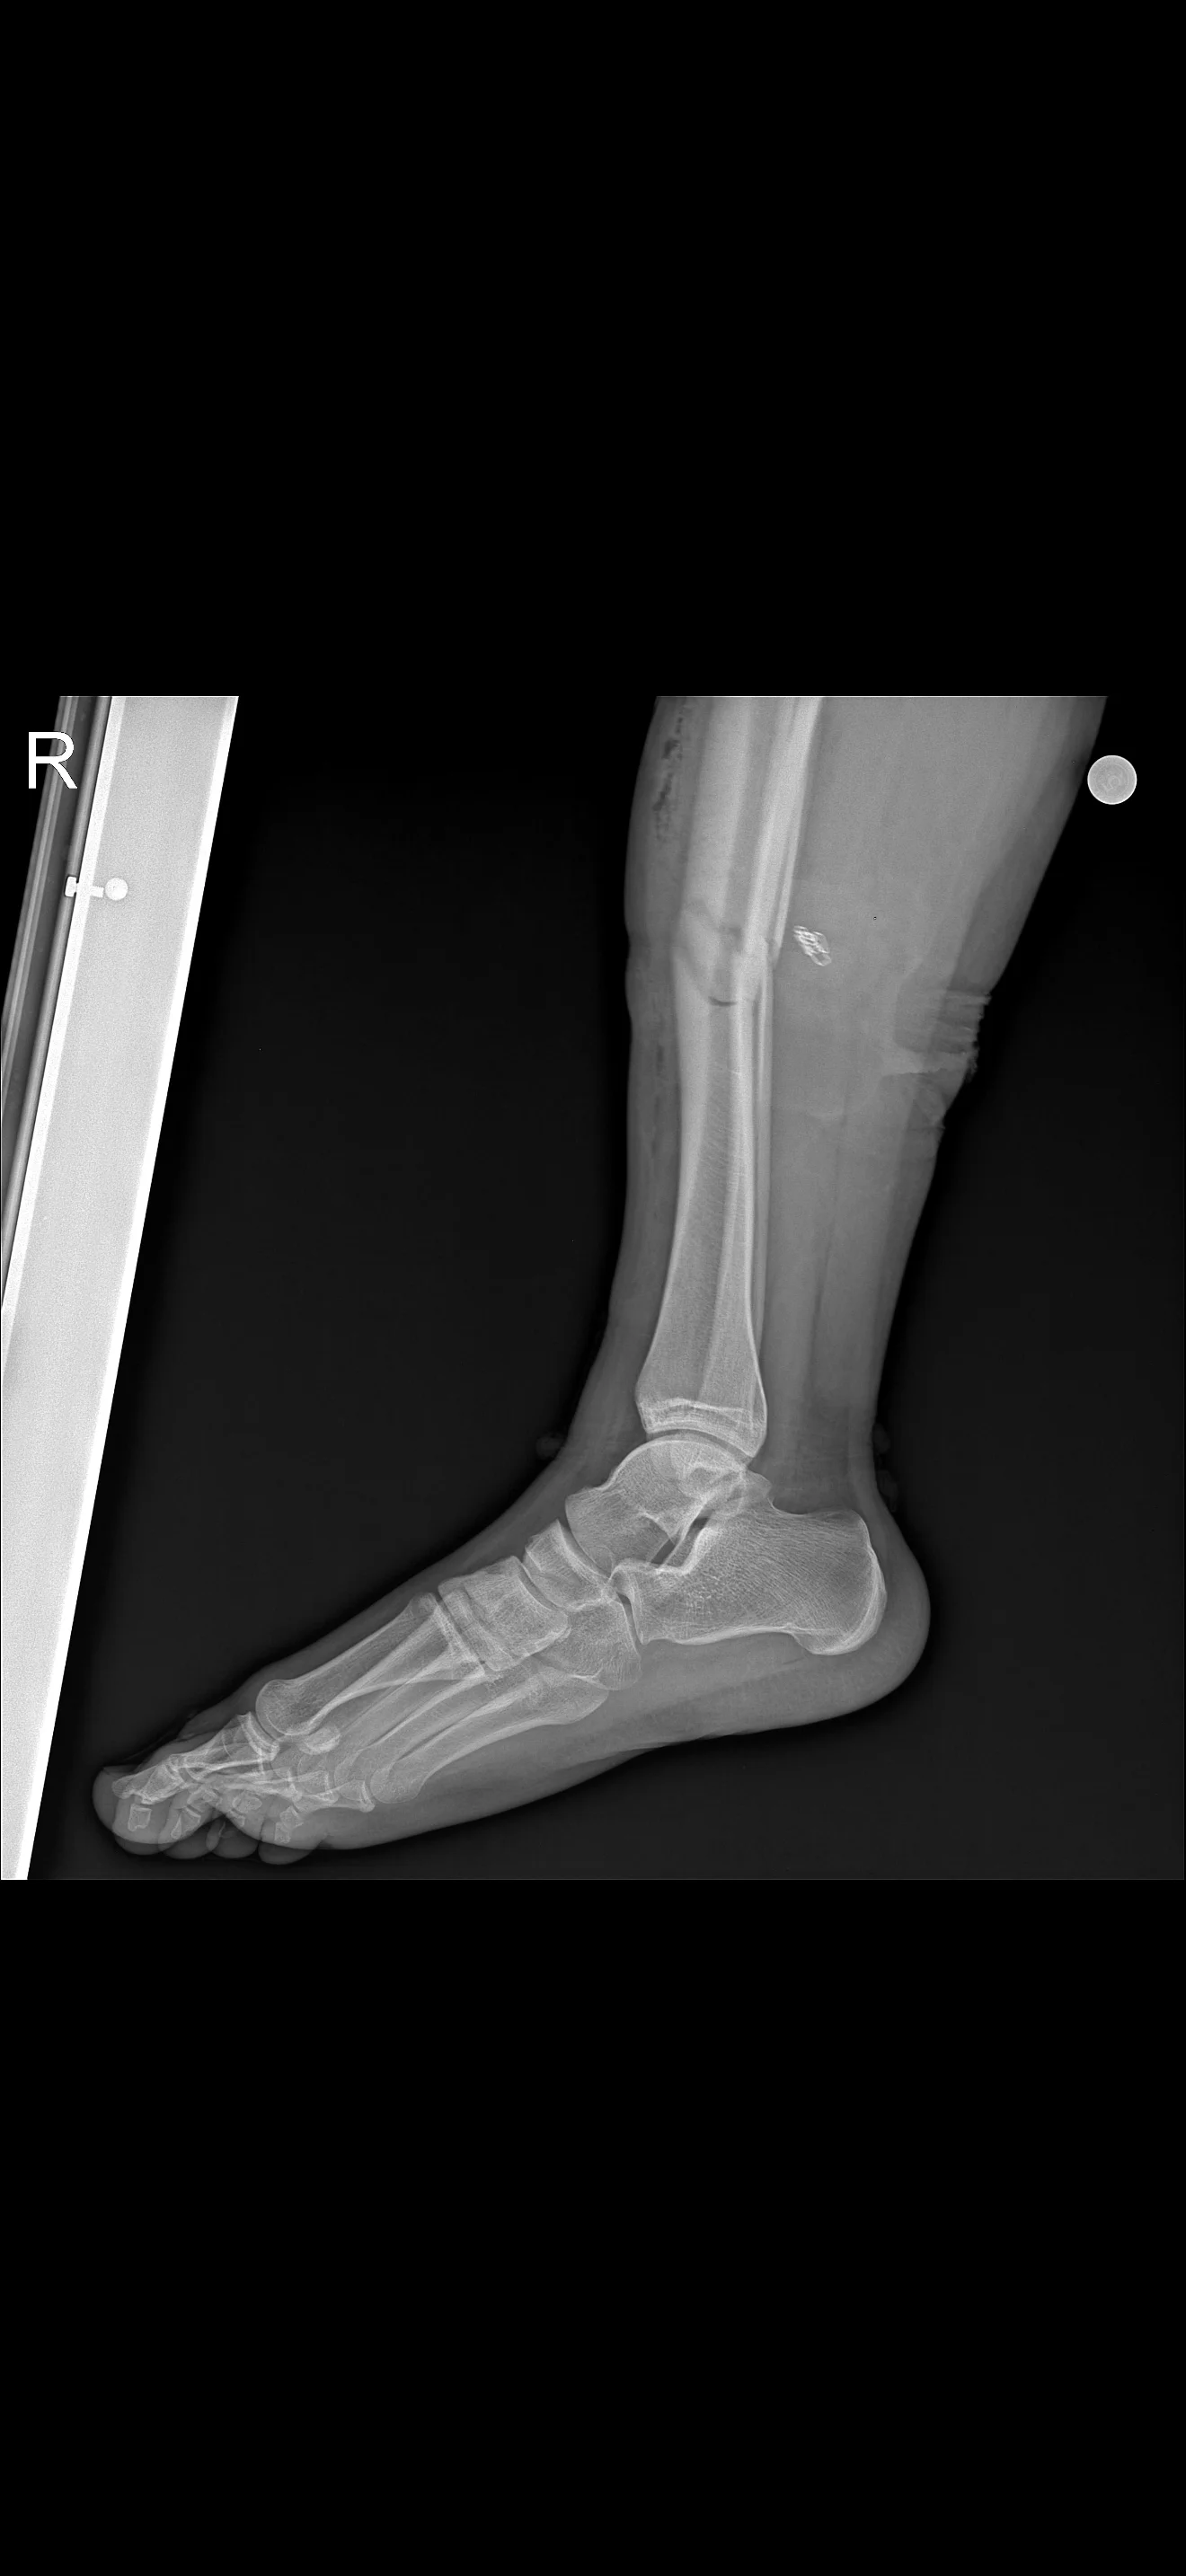

Valla benim bacağım 3 ay alçıda kaldı özeldeki doktor alçının 2. Ayında diz ve bilek bölümünün kesilmesi lazımdı dedi çünkü benim bacakta kireçlenmeyi geçtim 17 yaşındayım kemik erimesi bile başlamıştı verdiği kremler ile fln toparlanıyorum ama geçirtiyorlar fln ama malesef sağlık için gerekiyor bana ehliyetsiz biri çarptı yayaken bacak fena kırıldı

Ekler

• IMG_7615.webp

IMG_7615.webp

102 KB · Hit: 38